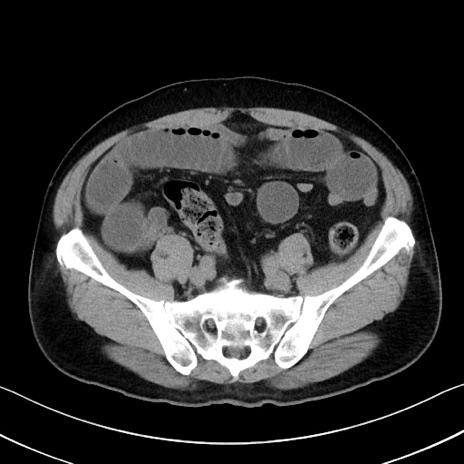

症例35(横断像)

【症例】70歳代 男性

【主訴】腹部膨満、嘔吐

【現病歴】昨日より腹部膨満感出現。本日増悪し、仙痛出現。嘔吐あり、受診。

【既往歴】糖尿病、胆摘後

【身体所見】BP 149/80mmHg、HR 74/min、BT 35.9℃、腹部:膨満、軟、圧痛なし。腸雑音減弱あり。上腹部正中切開瘢痕あり。

【データ】WBC 13500、CRP 1.72